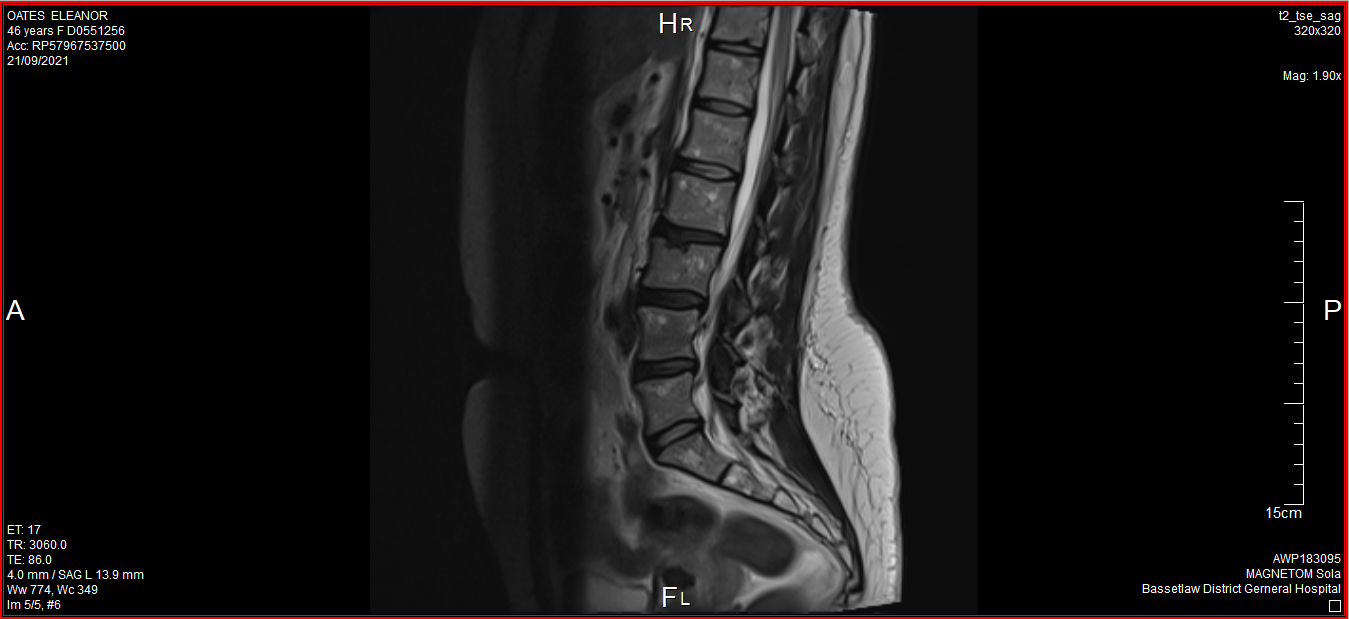

The above image has been taken from the latest MRI scan completed in September 2021 showing three of the desiccated discs.

The labral tear has been repaired but does cause intermittent pain and discomfort. The main issues with my back pain are inflammation in my sacroiliac joint, desiccated of vertebral discs and stenosis. The latter being extra bone growth that is narrowing the gap between some of the vertebrae.